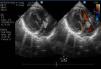

En el ecocardiograma se observó una lesión redondeada hiperecogénica, de aspecto homogéneo, situada en la región inferior del septo interauricular, próxima a la unión auriculoventricular y en relación con la válvula tricúspide, de dimensiones aproximadas de 9,4 × 11mm. No existía compromiso del llenado auricular ni ventricular así como tampoco de la válvula tricúspide (fig. 1). La función de ambos ventrículos era buena y no se detectaron otras lesiones.